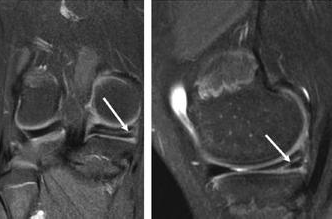

患者多数有明显外伤史。急性期膝关节有明显疼痛、肿胀和积液,关节屈伸活动障碍。急性期过后,肿胀和积液可自行消退,但活动时关节仍有疼痛,尤以上下楼、上下坡、下蹲起立、跑、跳等动作时疼痛更明显,严重者可跛行或屈伸功能障碍,部分病人有交锁现象,或在膝关节屈伸时有弹响。膝关节间隙处的压痛是半月板损伤的重要依据,膝关节MRI检查有重要意义。

近些年,关节镜技术的发展及治疗日新月异,非常适用于半月板损伤的治疗,半月板边缘撕裂可行缝合修复,通常进行半月板部分切除,保留未损伤的部分。对早期怀疑半月板损伤者可行急诊关节镜检查,早期处理半月板损伤,缩短疗程,提高治疗效果,减少损伤性

关节炎

的发生。通过关节镜手术创伤小,恢复快,为现在半月板损伤的首选治疗方法。